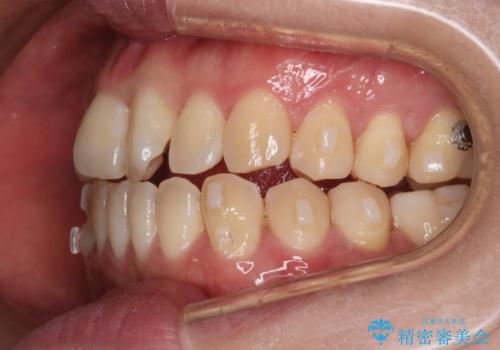

【インビザライン】前歯の捻れ気になる

- 上の前歯の捻れを主訴に来院されました。

前歯の捻れとがたつきを改善するために、IPR(歯と歯の間を削る処置)と歯列拡大をすることで歯並びを整えていく治療計画を立てました。

かみ合わせを整えるためにゴム掛けも行いながら、治療していきました。

患者様にマウスピースの使用とゴム掛けを頑張っていただいたおかげでリファイメント(マウスピースの再発注)も1回で終了することができました。